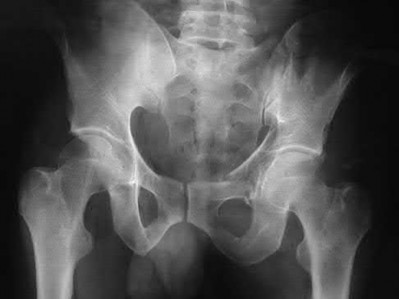

Which of the following images shows an injury pattern most consistent with a lateral compression type 3 pelvic ring injury?

Figure C is an axial CT scan of a lateral compression type 3 (LC3) pelvic ring injury.

Classically, LC3 injuries demonstrate an ipsilateral lateral compression and a contralateral APC (windswept pelvis) fracture pattern. The most common mechanism of injury in these cases is a rollover MVC or pedestrian vs. auto. LC1 injuries are characterized by an oblique or transverse ramus fracture and ipsilateral anterior sacral ala compression fracture, while LC2 injuries consist of a rami fracture and ipsilateral posterior ilium fracture dislocation (crescent fracture). While LC1 injuries can often initially be managed conservatively with protected weight-bearing and close observation, LC2 and LC3 pelvic ring injuries are almost universally operative.

Pennal et al. discuss a radiologic technique for assessing the forces producing pelvic disruption and its use in logically classifying pelvic injury. Based on this radiologic assessment and along with some biomechanical studies, they propose a classification system involving three major forces producing injury that can also be helpful in the management of these patients.

Young et al. performed a retrospective analysis of the plain radiographs of 142 cases of pelvic fractures and identified four patterns of force that presented with distinctive, recognizable radiographic appearances. They describe a classification system for pelvic fractures based on radiographic and clinical findings that correlates with associated injury to soft-tissue structures and enables the surgeon to begin corrective procedures rapidly.

Incorrect Answers:

Answer 1: This represents a lateral compression type 2 injury. Answer 2: This represents a lateral compression type 1 injury.

Answer 4: This represents an anterior posterior compression type 2 injury. Answer 5: This represents an anterior posterior compression type 3 injury.